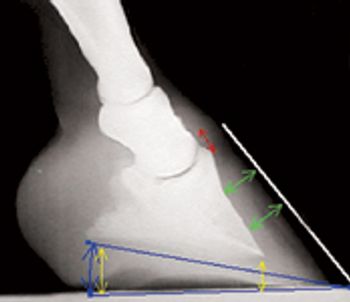

One practitioner's 13-step protocol to help horses suffering from this painful condition.